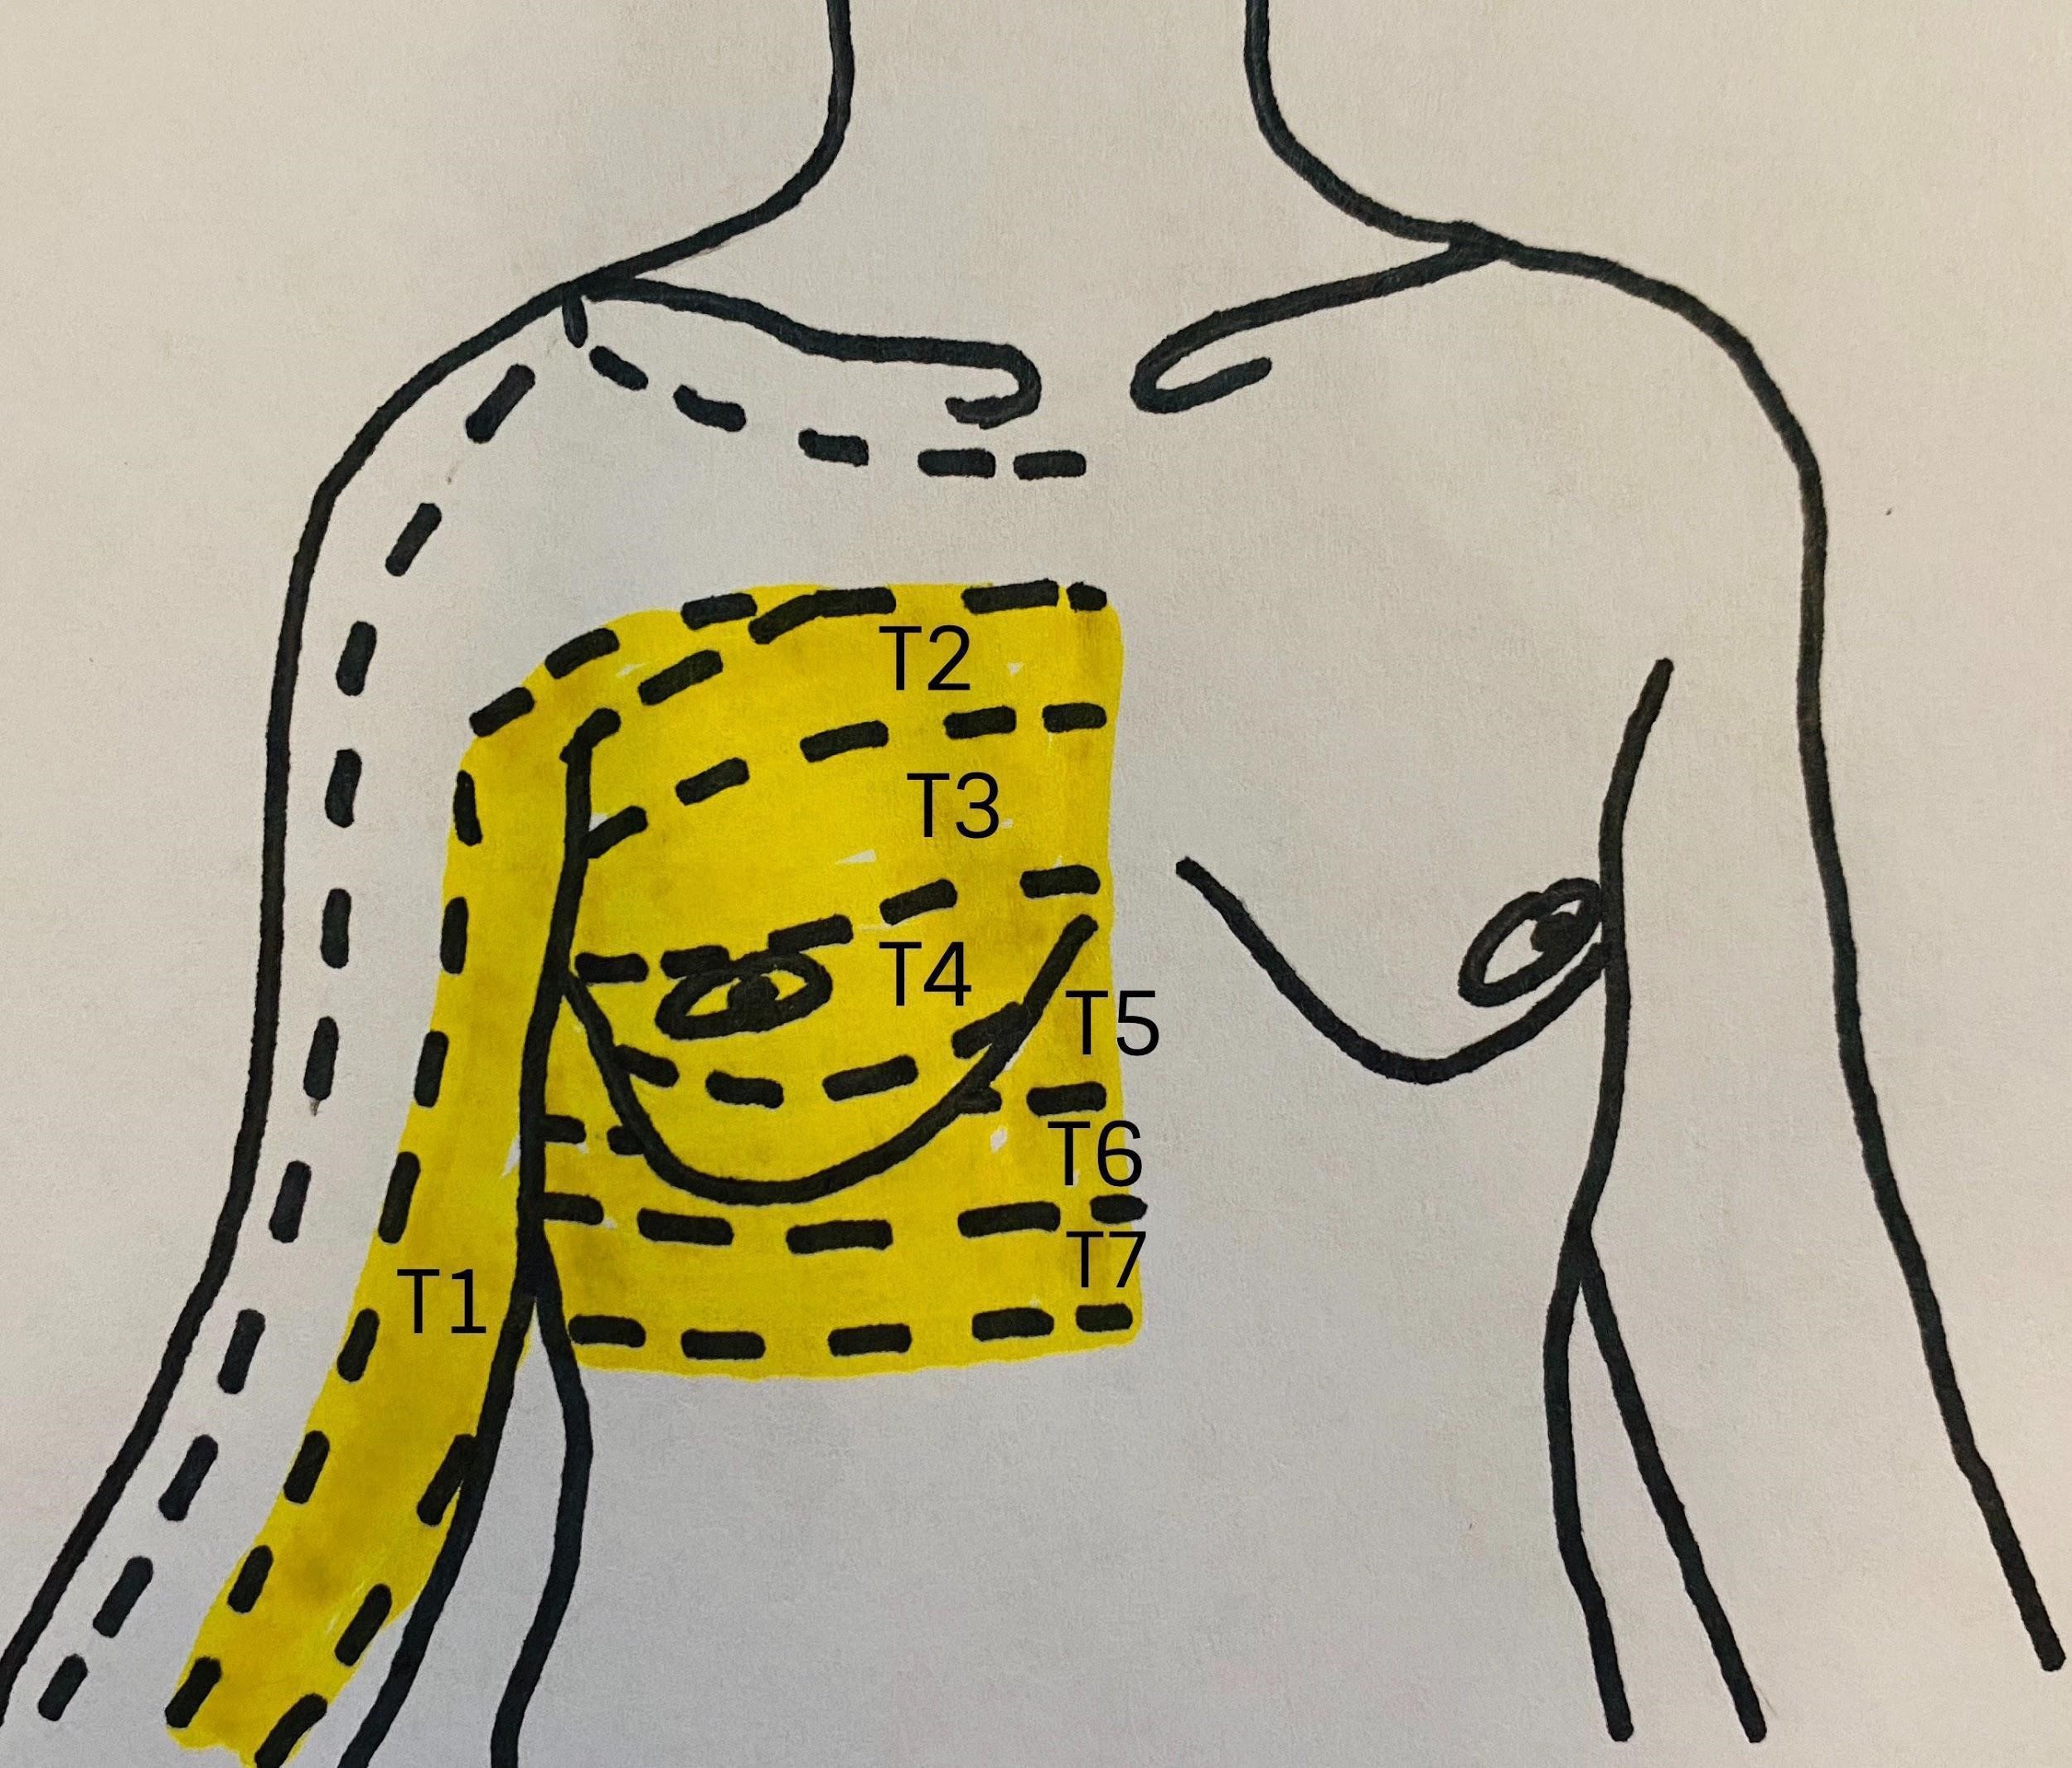

A variety of RA techniques may provide effective analgesia for breast surgery. The options highlighted in Figure 2 and Table 2 include paravertebral blockade (PVB), erector spinae plane block (ESPB), and pectoral nerve block (PECS II). Epidural analgesia and serratus plane blocks are additional techniques for effective breast analgesia.

Figure 2: Anatomic locations of common regional and neuraxial blocks used for breast surgery

Reprinted with permission from EPFL, Visible Human Visualization Software, http://visiblehuman.epfl.ch and Gold Standard Multimedia (GSM) http://www.gsm.org.